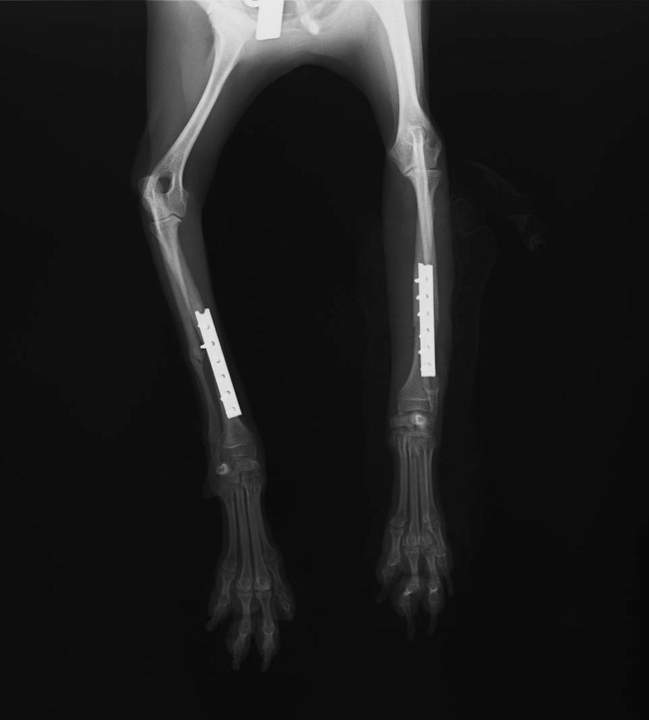

私の愛犬トイプードルのLOUIS(ルイ)は、4月に2段ケージから落ちて右前足を骨折して病院に来ました。X線写真を見て、体重が2kg無いルイの骨はとても細くて痛々しかったです。数日後、里親になることも正式に決まり、院長先生にチタンプレートを骨に固定する手術をしてもらいました。

そんな手術から約1ヵ月経ったある日、私が少し出かけていて、両親がほんの一瞬目を離したすきに30センチほどのソファから飛び降り、今度は左前足骨折。きっと、右足がまだ完治してない状態でかばって左手だけで下手に着地したのだと思います。そんなルイがかわいそうで、看護師なのに注意不足だったと反省しました。再度同じ手術をして頂き、ルイの腕のX線写真はまるでサイボーグのようになりました。

チタンプレートは治ったあとも体の中にずっと入れておいても負担が少ない素材なので、ルイは生涯このプレート達と歩いていきます♪我が家では、ソファを低 いものに替えて、目を離すときはケージのなかに入れるようしています。もう二度と痛い思いしないように気をつけようね~

![]() |

左右の前足にプレートとスクリューが入っています | 骨折した骨がきれいに寄っています | ギプスがやっととれました~ |